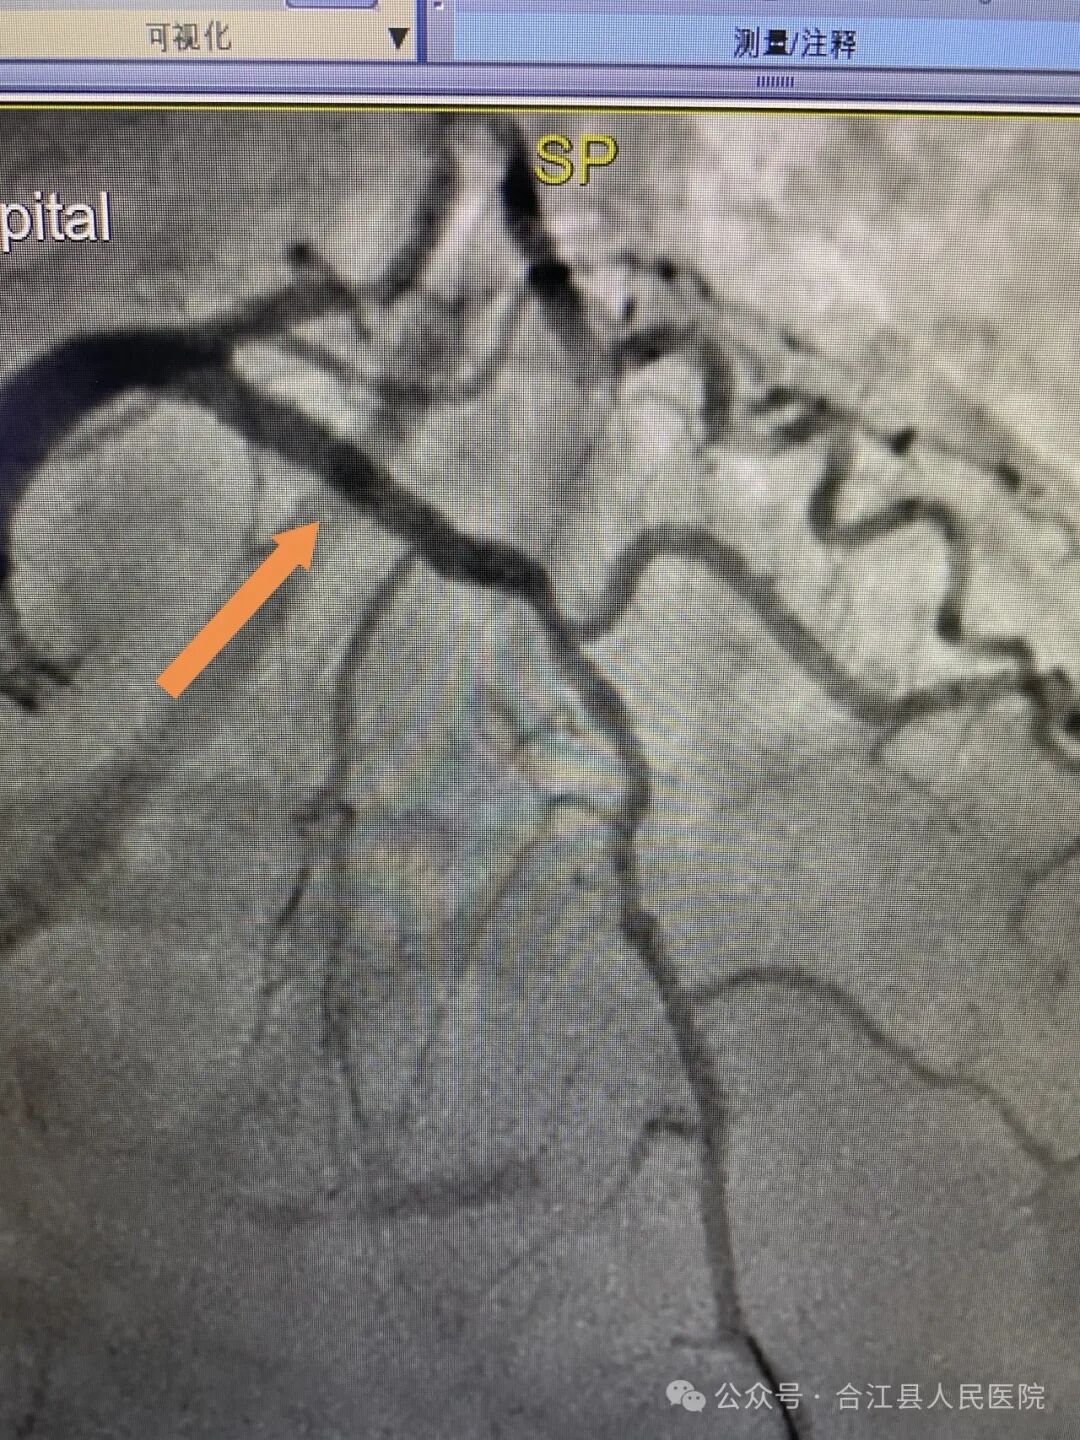

胸痛中心医疗总监、副主任医师张永强火速赶到介入手术室,对老人进行了问询和查体,与家属沟通后决定行急诊冠脉造影,造影结果显示:LAD近段严重狭窄95%。随后,再次取得患者家属同意后,经验丰富的张永强对其成功实施了急诊冠脉支架植入